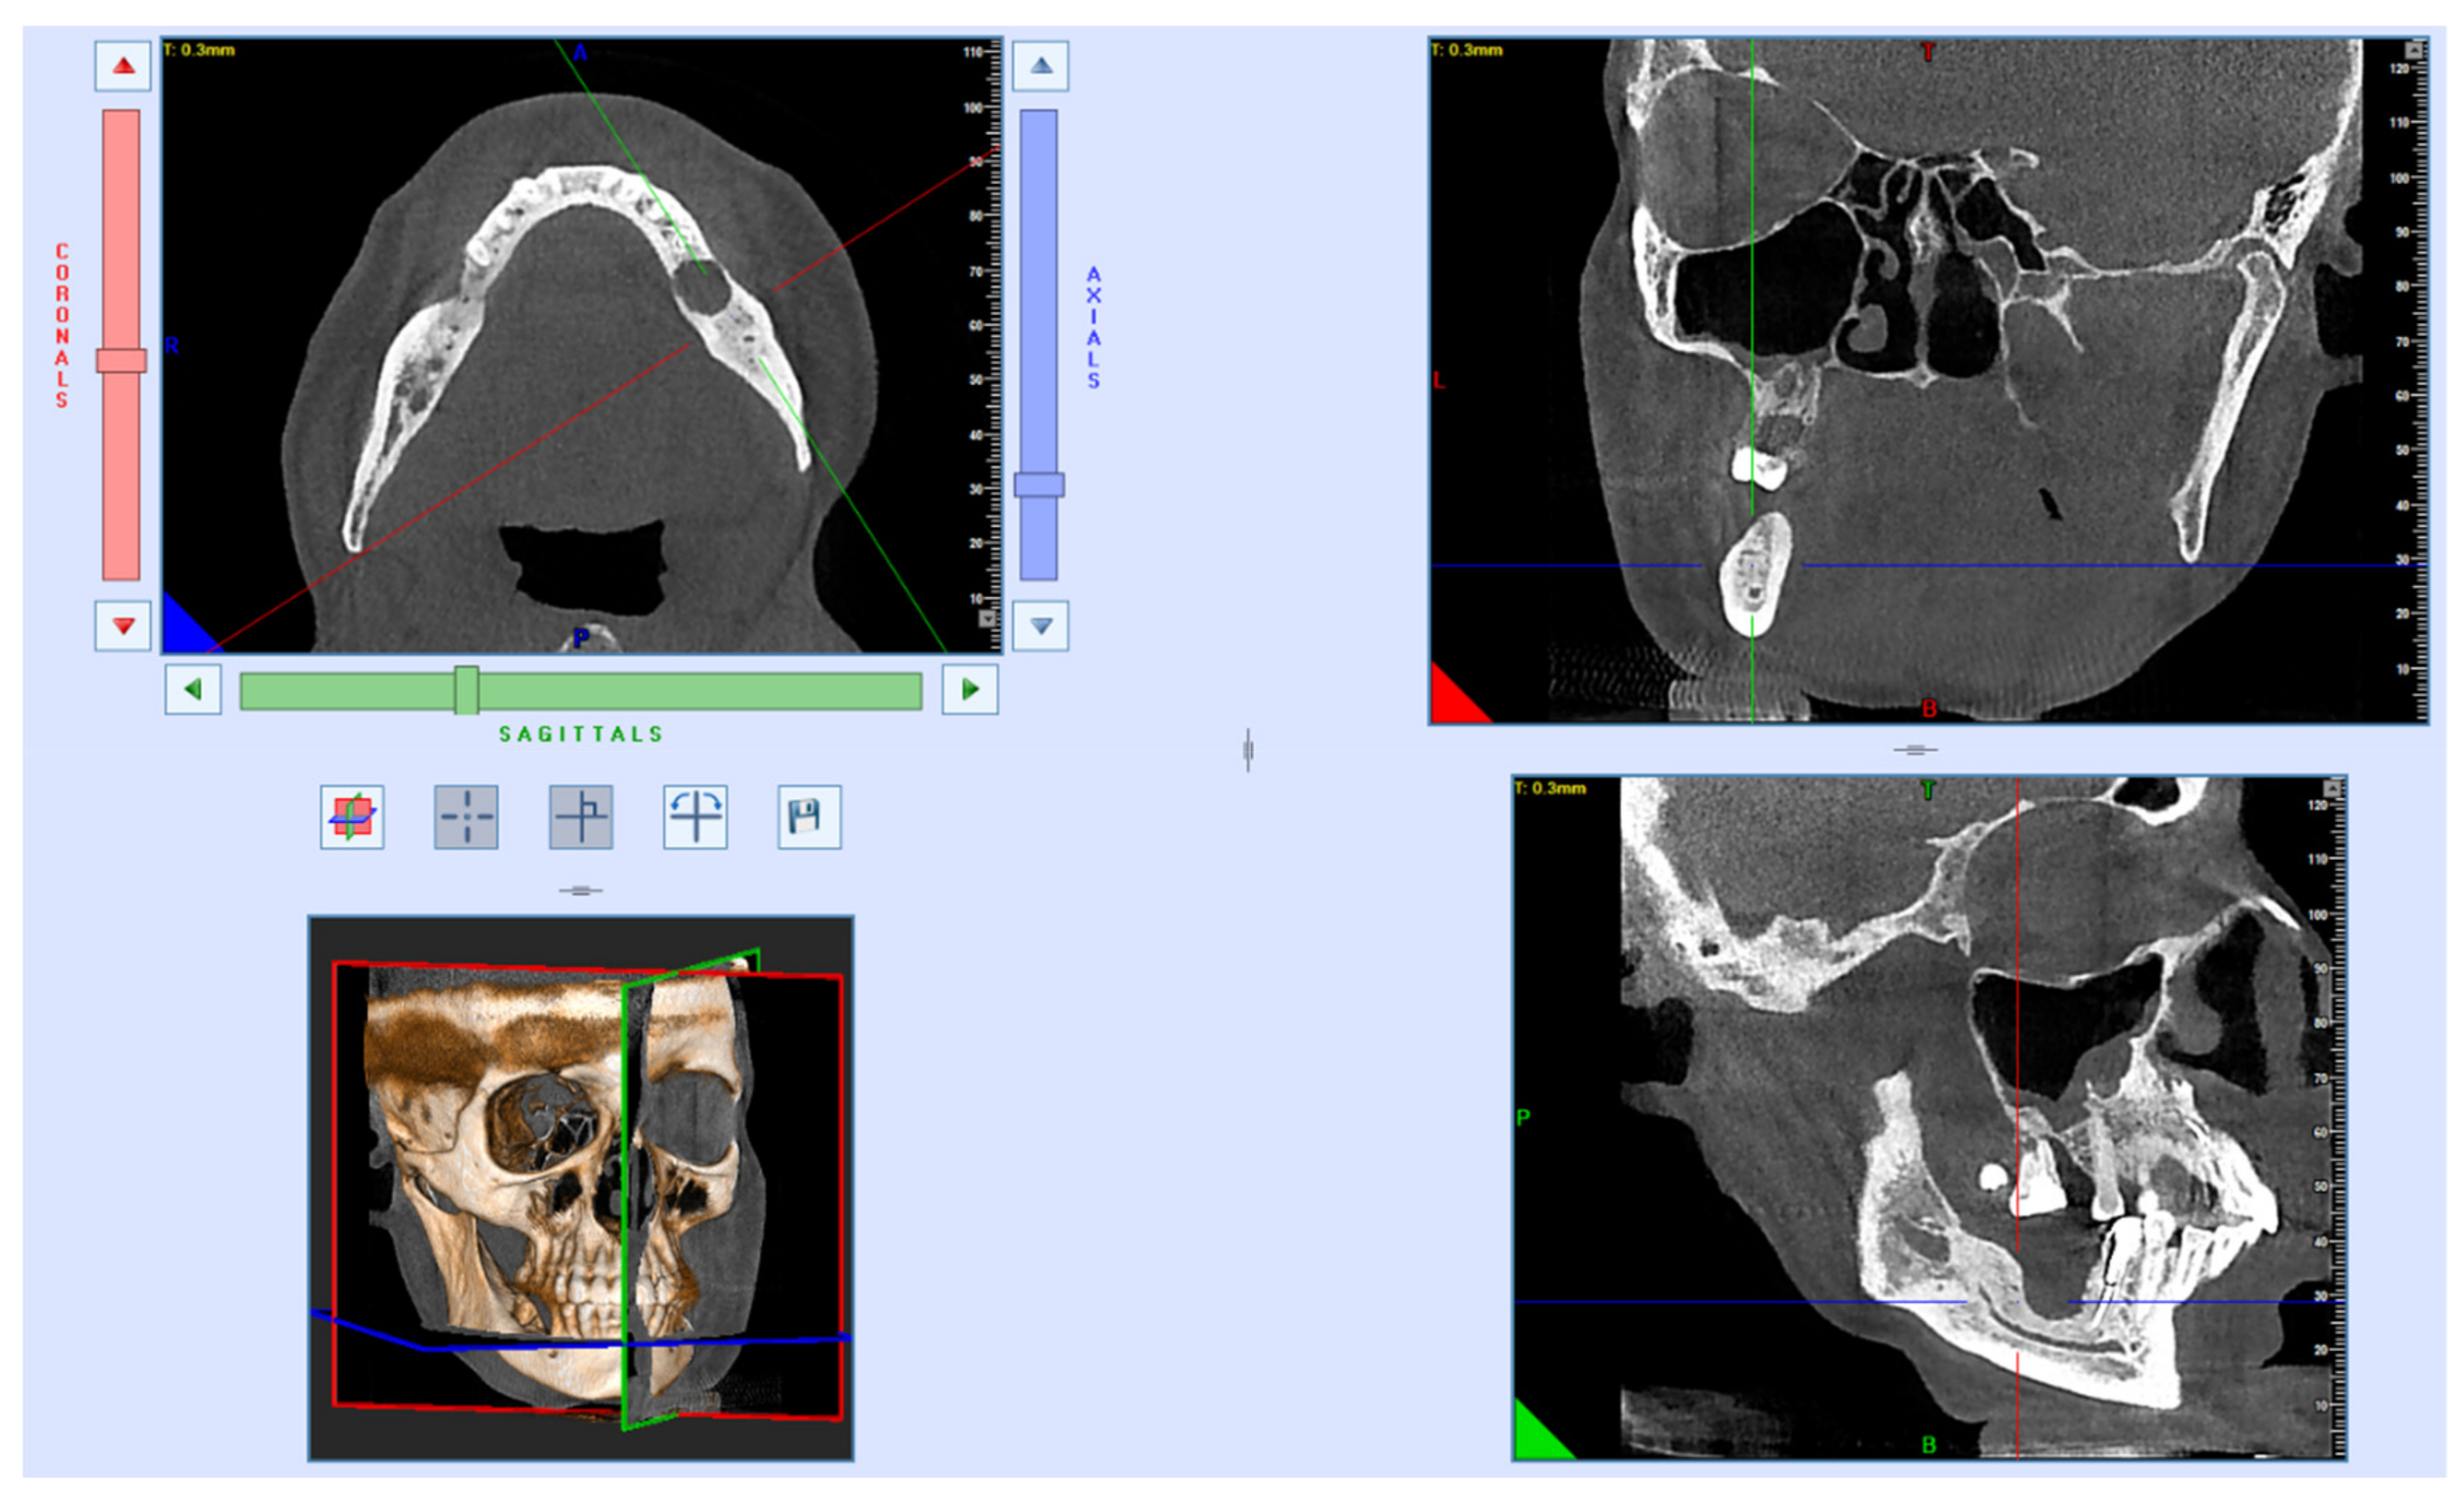

Multi-spiral computed tomography of the lower jaw determined an oval-shaped bone lesion at the root level of teeth 3.7 and 3.8, with dimensions of 20 × 16 × 16 mm. The bone was swollen at the level of teeth 3.6–3.8, a periosteal reaction was noted, the contours of the jaw were enlarged, and the cortical plates were thinned. Pathological fracture of the lower jaw, with fragment displacement, occurred; the fracture line passed through the sockets of teeth 3.7 and 3.8 (Figure 2).

Figure 2.

Patient’s CBCT at admission.